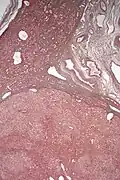

| Micrograph of a hepatic adenoma (bottom of image). H&E stain | |

Pathologic diagnosis

Hepatic adenomas are, typically, well-circumscribed nodules that consist of sheets of hepatocytes with a bubbly vacuolated cytoplasm. The hepatocytes are on a regular reticulin scaffold and less or equal to three cell thick.

The histologic diagnosis of hepatic adenomas can be aided by reticulin staining. In hepatic adenomas, the reticulin scaffold is preserved and hepatocytes do not form layers of four or more hepatocytes, as is seen in hepatocellular carcinoma.

Cells resemble normal hepatocytes and are traversed by blood vessels but lack portal tracts or central veins.

Micrograph of hepatic adenoma. H&E stain -